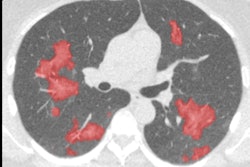

To standardize the appearance of chest x-rays, the image is decomposed into frequency bands using a process of hierarchical unsharp masking. In a training set, the average energy or standard deviation of each frequency band in the central part of the image is determined. All bands are then scaled to this reference energy, and the input image is reconstructed from the scaled frequency bands. After energy normalization, the chest radiographs look much more similar to each other. All images courtesy of Rick Philipsen.The central 70% of energies in each image are selected and the rest are discarded from the image data, according to Philipsen.

The application of energy normalization improved CAD's ability to distinguish normal (top row) from abnormal (bottom row) chest radiographs.Energy normalization works well, improving the robustness of the CAD system for tuberculosis, Philipsen concluded. The process "can be used reliably on data from different x-ray units and has great potential in TB screening," he said.